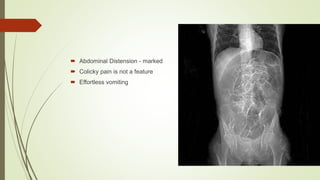

 Abdominal Distension - marked

 Colicky pain is not a feature

 Effortless vomiting